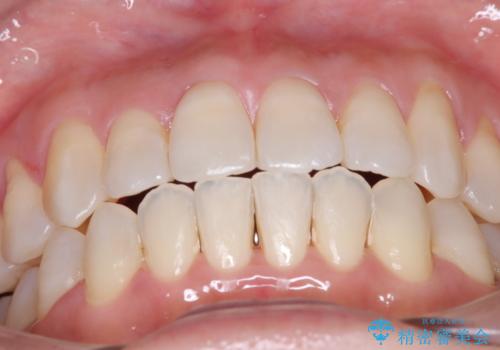

【開咬】笑った時の見た目を改善したい。

- 重度の開咬でしたがインビザラインで適切に治療計画を立て、きれいに仕上がりました。

インビザラインは開咬の治療に向いています。